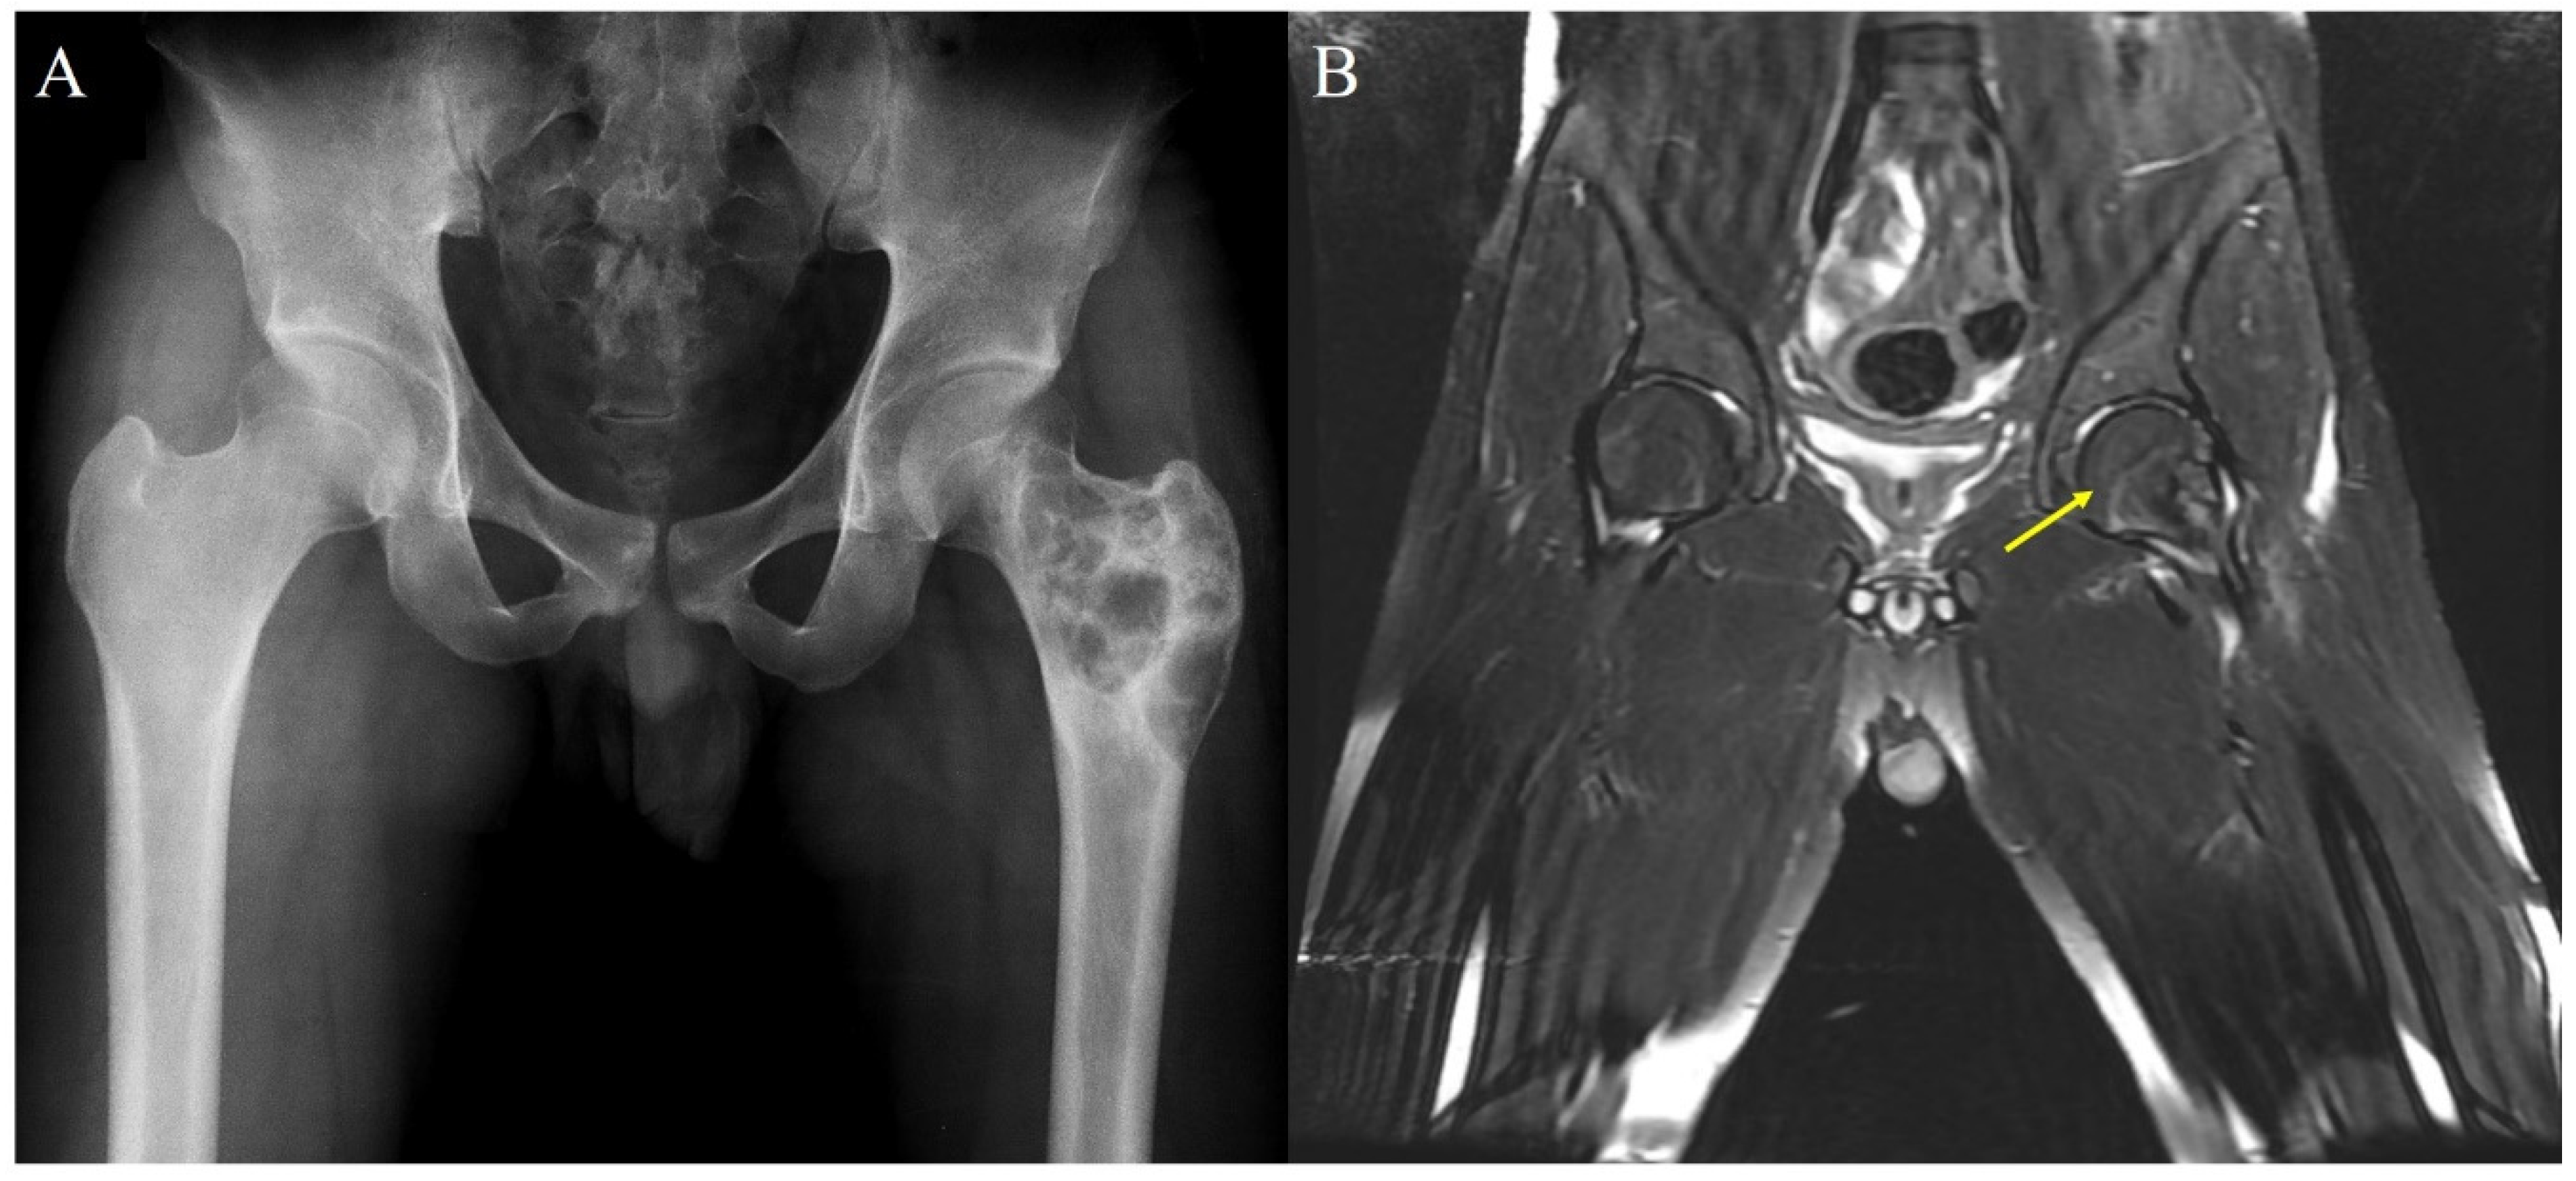

| 6 | 14 | M | Distal femur + Prox Tibia (Rt) Tibia + Prox Fibular (Lt) | EM (Femur, Tibia, Fibular) | P | 1 | Curettage + Excision (LR) + Prosthesis (LR) | 57 | 1 week pain, LR 28 mo |